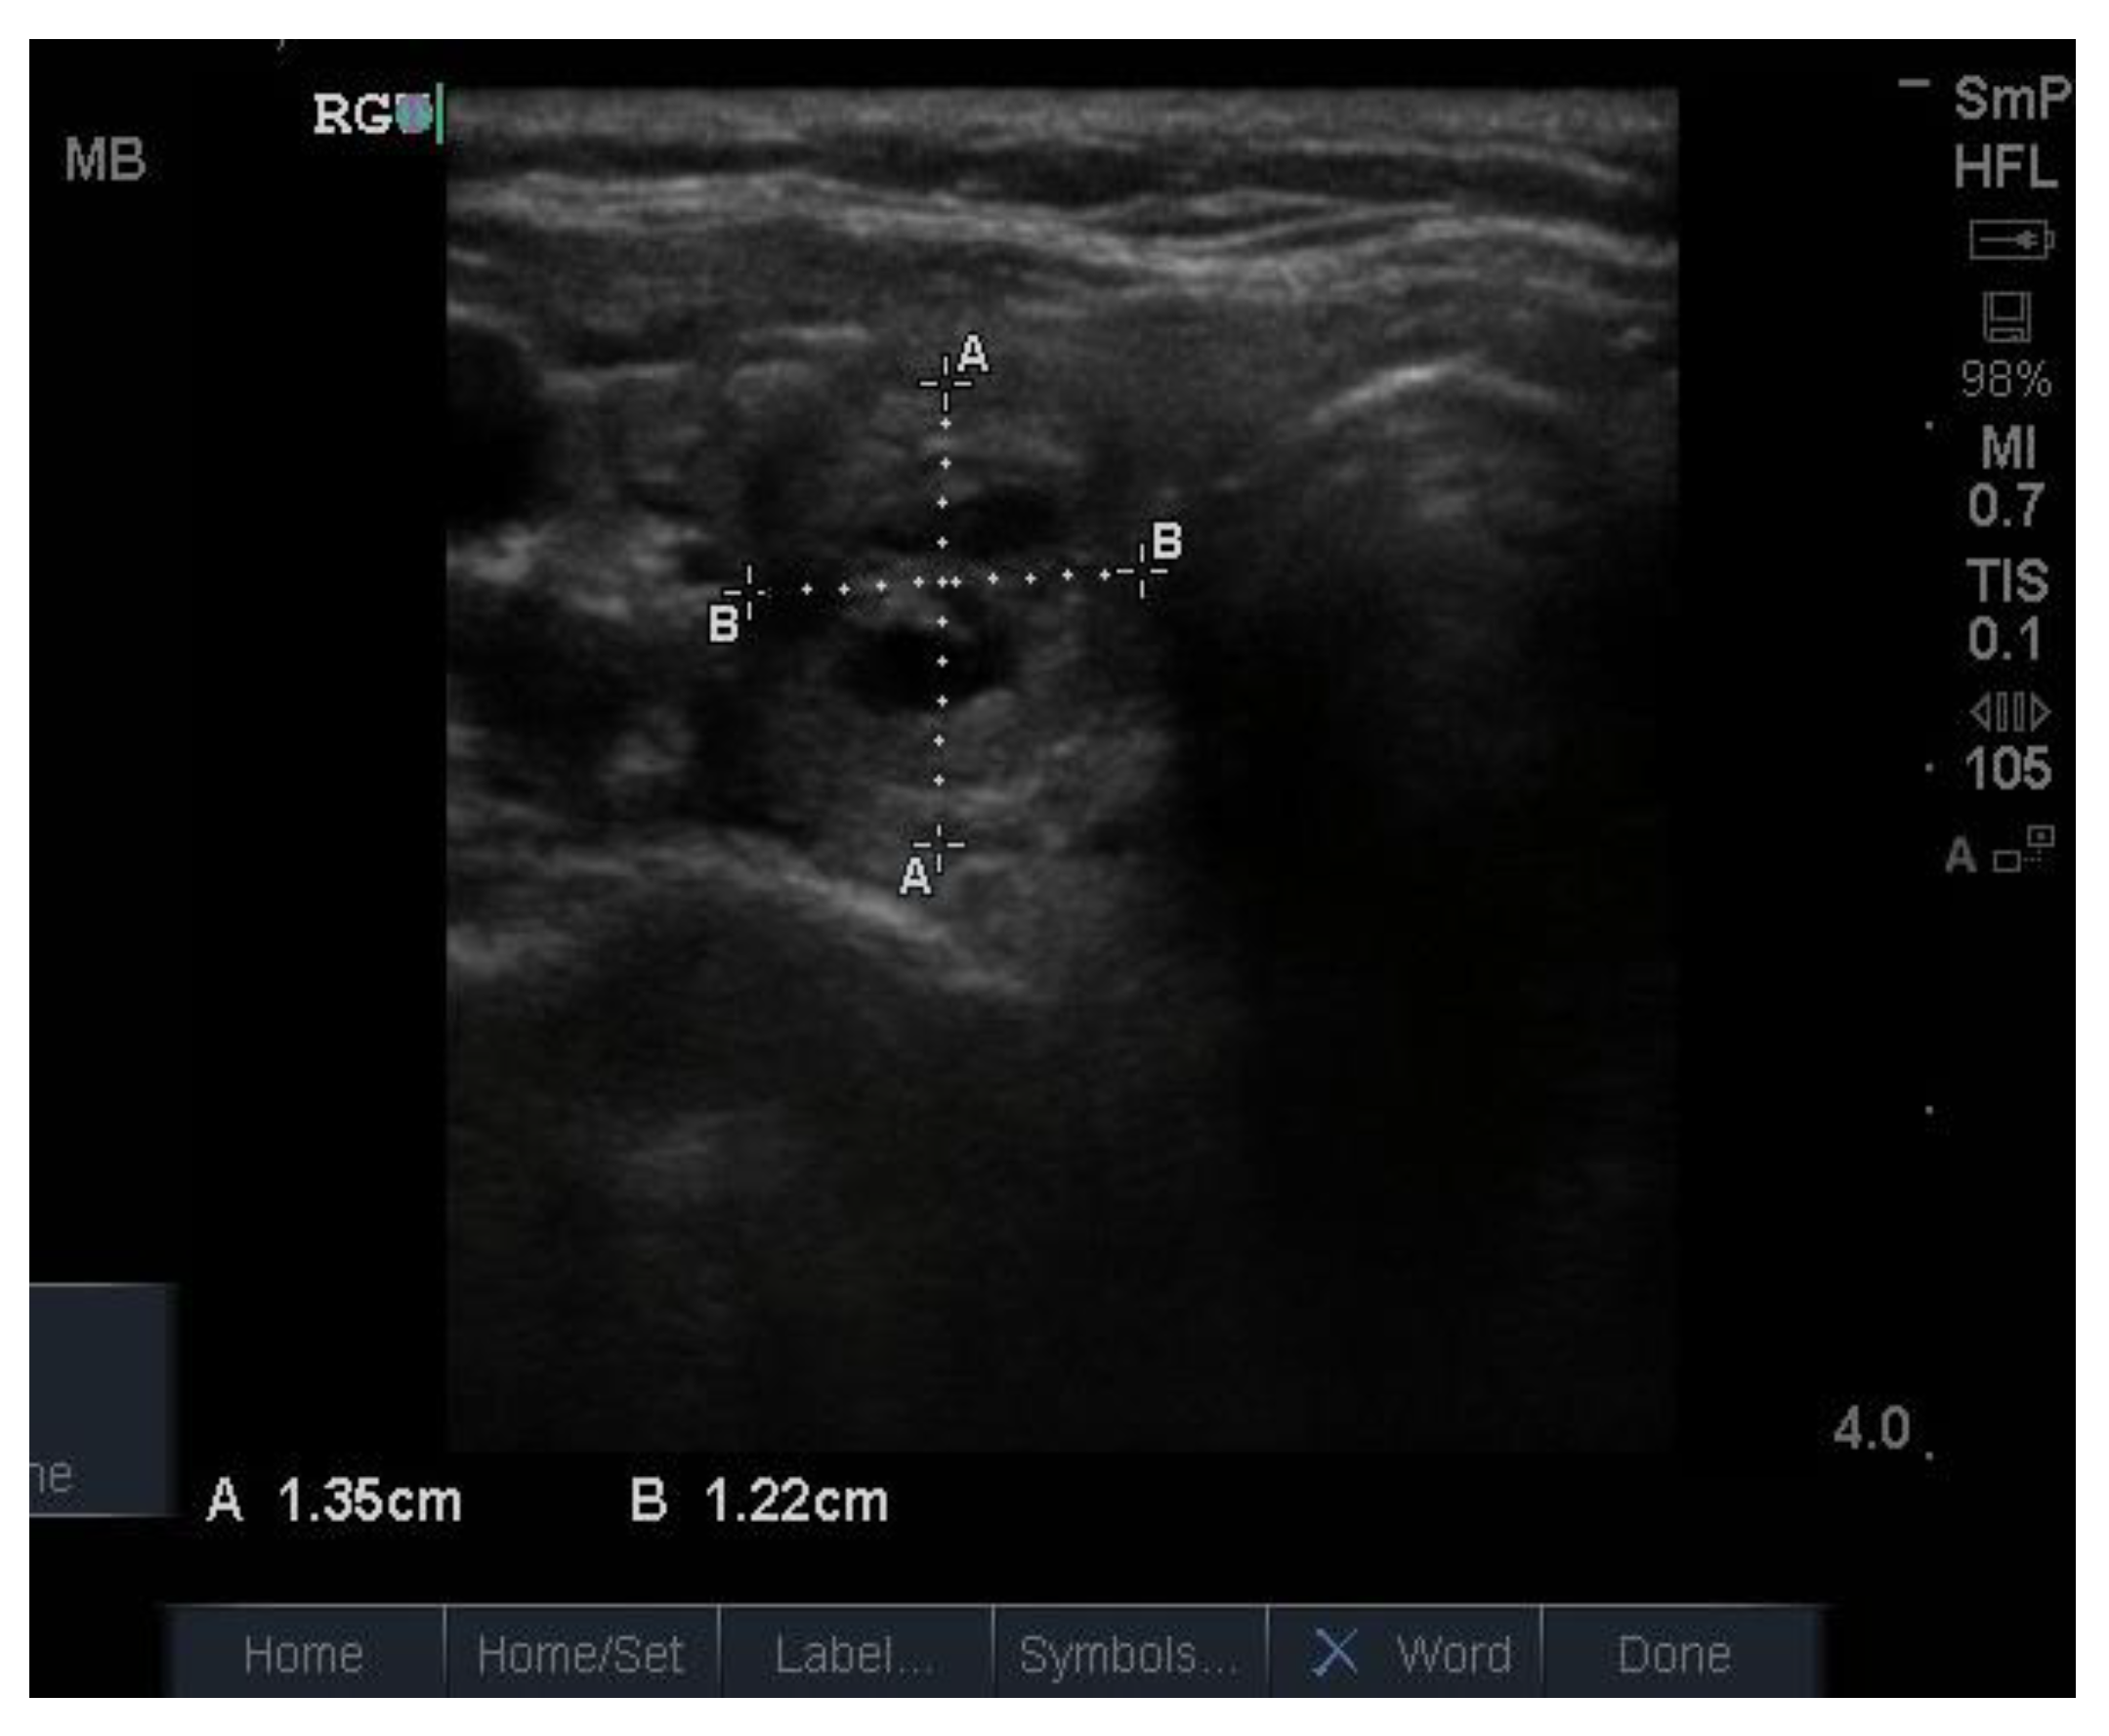

Because the senior author (JW) routinely measures serum calcium, parathyroid hormone (PTH) and vitamin D in his patients, hyperparathyroidism due to a benign adenoma of one of the parathyroid glands appears to be much more common than previously thought. The parathyroid glands are hidden behind the thyroid and so may be obscured by thyroid nodules, although they can often be seen in the longitudinal view below the lobes, as a hypoechoic lesion of around 1 cm in diameter (Figure 18).

Figure 18.

Thyroid ultrasound from a patient with hyperparathyroidism showing a hypoechoic lesion below the right thyroid lobe that was confirmed to be a parathyroid adenoma at surgery.

The parathyroid adenoma is typically hypoechoic by comparison to the nearby thyroid tissue, which is consistent with the author’s experience. However, only about 50% of subsequently proven parathyroid adenomas are seen on ultrasound and even the Sestamibi nuclear scan fails to pick them up in about 30% of cases.